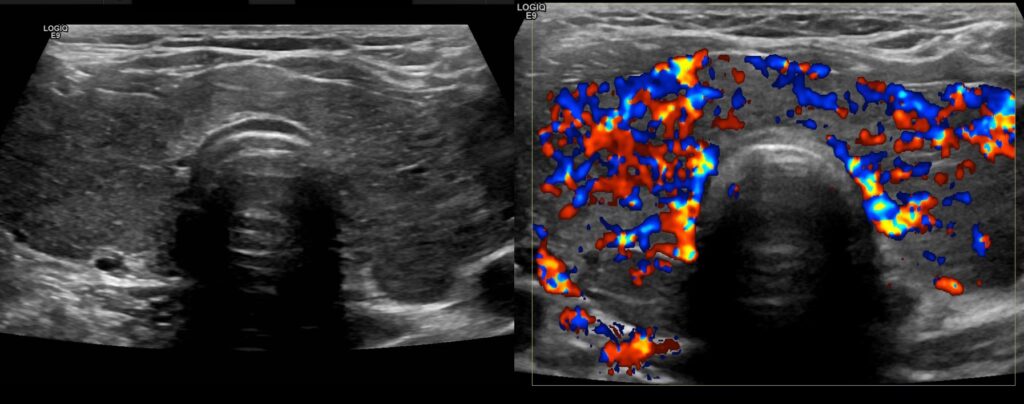

- Blodgennemstrømning (vaskularitet): Ved hjælp af farve-Doppler kan lægen vurdere blodforsyningen til knuden. En kaotisk og primært central blodforsyning i knuden kan være et tegn på malignitet, mens blodforsyning primært i periferien (omkring knuden) oftere ses ved godartede læsioner.

- Autoimmune sygdomme (Hashimoto's og Graves'): Ved autoimmune sygdomme som Hashimoto's thyroiditis (den hyppigste årsag til lavt stofskifte) og Graves' sygdom (den hyppigste årsag til højt stofskifte) får skjoldbruskkirtlen ofte et karakteristisk udseende på ultralyd. Vævet kan fremstå diffust hypoekkoisk og heterogent (plettet). Ved Graves' sygdom kan farve-Doppler vise en dramatisk øget blodgennemstrømning, et fænomen der sommetider kaldes "thyroid inferno".